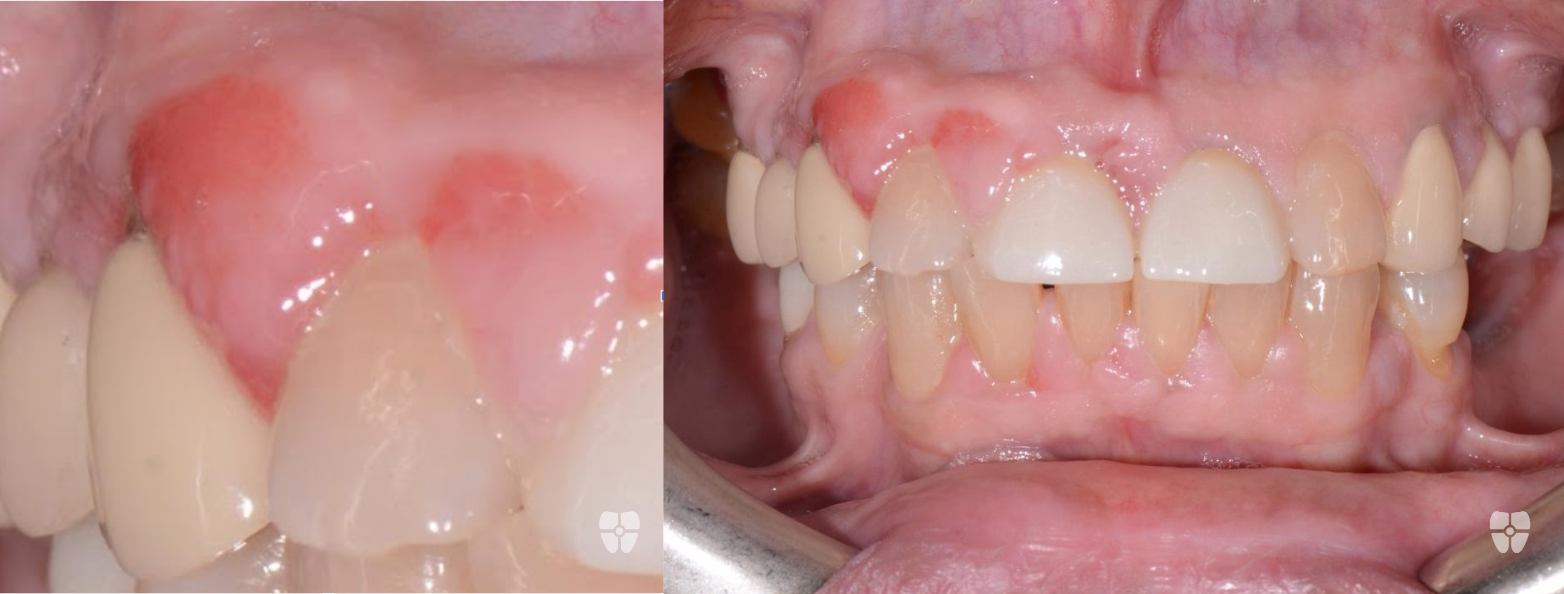

Non-Surgical Flapless Graft using Biological Materials and Periodontal Endoscopic Therapy:

The Results - 9 Months Apart

Real patient results achieved non-surgically with periodontal endoscopic therapy and biologics.

Periodontal endoscopes permit minimally invasive periodontal treatments. With this technology, clinicians can access and clean the periodontal pockets more precisely, removing debris, calculus, and damaged tissue without the need for more invasive surgical procedures. This approach reduces patient discomfort, chair time and accelerates the healing process.